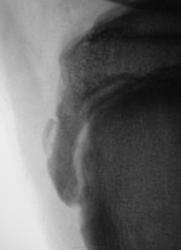

Пациент хирургом направлен на рентгенографию коленного сустава.

Полагаю, болезнь Шляттера. Хотелось бы сравнить со здоровой конечностью.